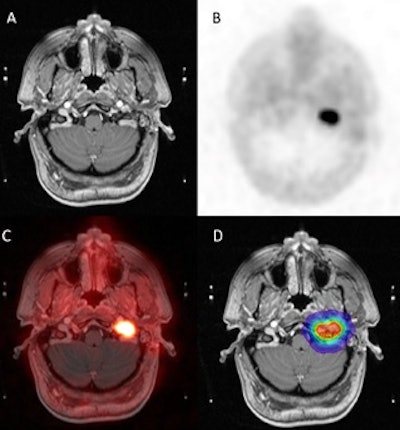

Axial imaging of glomus jugulare and treatment planning. A) T1-weighted MRI with contrast. B) Ga-68 DOTATATE PET/CT. C) MRI-PET fusion. D) Gamma knife radiation dose distribution. Image courtesy of Patrick Wojtylak.

In a comparison with contrast-enhanced MRI images alone, Ga-68 DOTATATE PET/CT offered superior lesion detection and more accurate delineation of tumor extent, according to the findings. Specifically, out of the 25 patients evaluated postoperatively, Ga-68 DOTATATE PET/CT identified unifocal (single lesion) residual or recurrent involvement in 11 patients and multifocal (multiple lesions) involvement in 14 patients.

“Ga-68 DOTATATE PET/CT more effectively distinguishes between recurrent or residual tumors and scar tissue following surgery, offering higher sensitivity and specificity than MRI,” Wojtylak said.